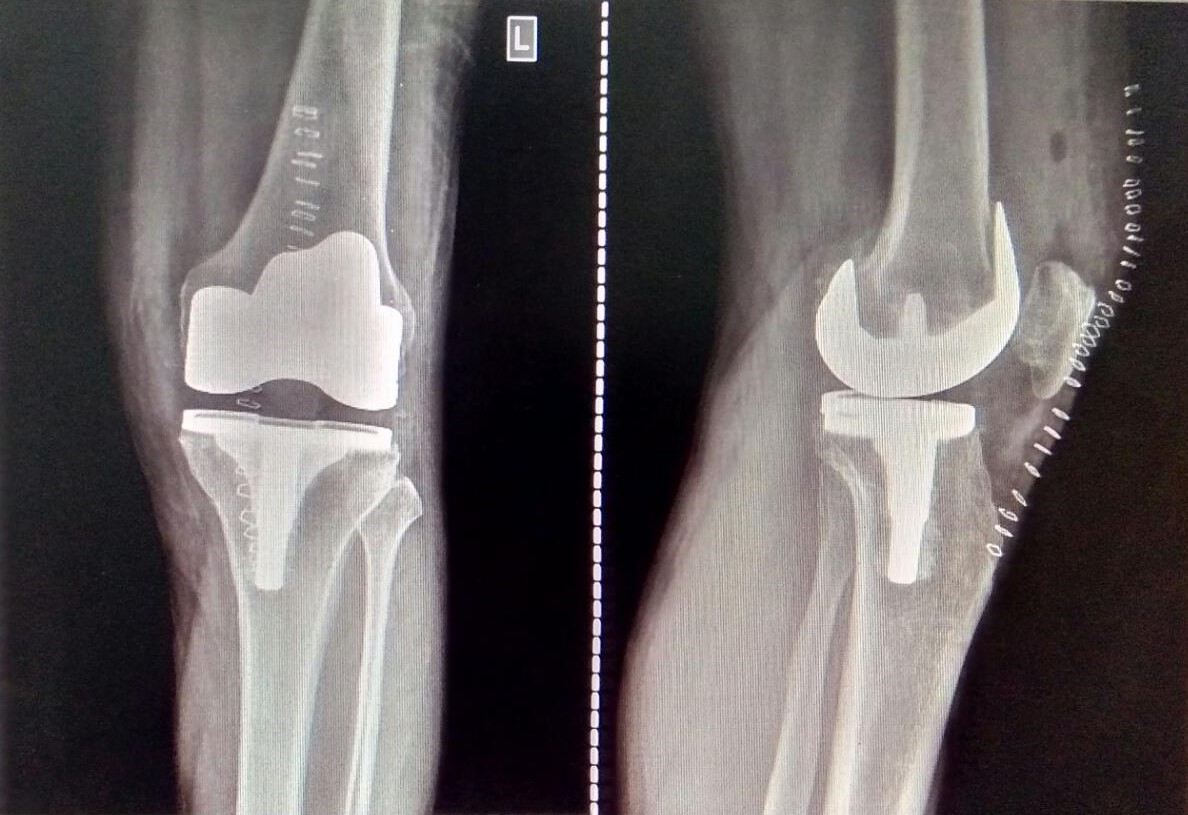

Knee and Hip Replacement